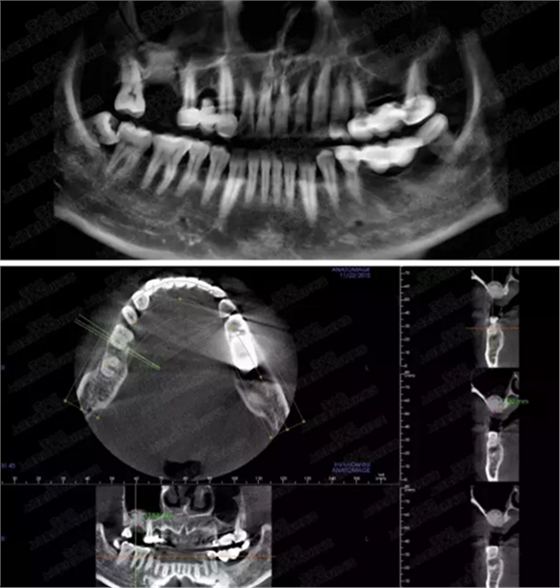

病例三

剩余骨量3mm

005.png

006.png